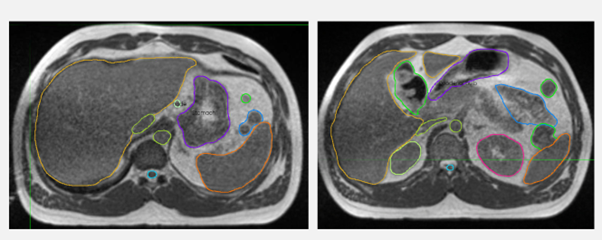

Fig 2: Planning MRI with the target and nearby organs at risk

On the first day of treatment, the shape and volume of the stomach was found to be very different from the planning scan. Complete recontouring was carried out to reflect the shape and volume of the stomach on the day. Surrounding organs at risk (OARs), heart, kidneys, spleen, and spinal cord, were also amended as required. The treatment plan was re-optimised to get the best dose to the target and as low dose as possible to the surrounding organs. This step overcomes the challenge of the daily change in the anatomy of the stomach.

The target and nearby OARs were recontoured daily for all 12 fractions of treatment to accommodate the change in anatomy and the treatment plan was re-optimised to the new contours. As the size and shape of the stomach changed significantly every day, it needed complete recontouring rather than editing. The total time on bed for each session was 60 minutes.